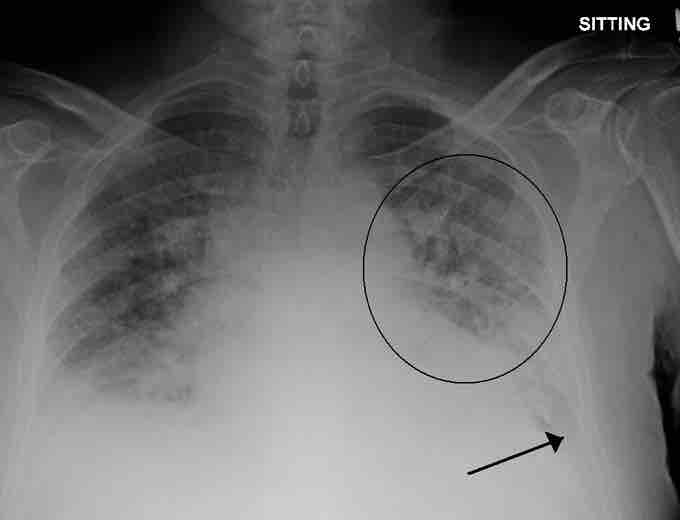

Pulmonary edema

A physiological shunt can develop if there is infection or edema in the lung which decreases ventilation, but does not affect perfusion; thus, the ventilation/perfusion ratio is affected. Pulmonary edema with small pleural effusions on both sides (as shown) can cause changes in the V/Q ratio.